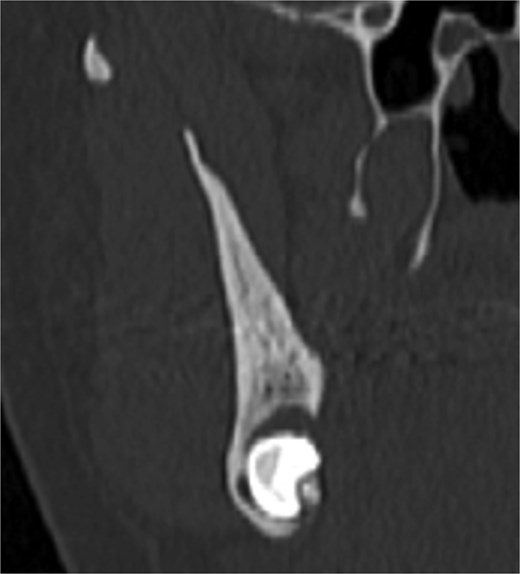

A 49-year-old male patient was referred, after a radiographic finding in a panoramic radiography, for evaluation of the lower right third molar (48) in an ectopic position associated with a radiolucent image, which suggested a cystic lesion (Fig. 1). A cone-beam computed tomography was made. The 3D imaging exams showed the presence of tooth 48 in the mandibular base, in the right angle region, associated with the radiolucent image, lingual fenestration, and intimate relationship between the third molar and the mandibular canal (Fig. 2). Due to the dental position, to have better visualization and less morbidity a submandibular extraoral approach was planned. The tooth removal and cyst curettage were made through the Risdon approach (Fig. 3). A fixation system with reconstruction plate (2.4 mm) was used to prevent a mandibular pathological fracture (Fig. 4). Anatomopathological examination of the cystic capsule was performed with a diagnosis of dentigerous cyst. In the postoperative period, the patient reported alteration in the sensitivity of the inferior alveolar nerve. Postoperative radiographic examinations showed adequate adaptation of the fixation system and complete surgical removal of the tooth and associated lesion. Orthopantomography with 4 months follow-up showed bone repair and adequate adaptation of the fixation system (Fig. 5).

The ectopic third molar usually is asymptomatic and difficult to identify. However, the clinical symptoms include swelling, limited mouth opening, pain, discharging fistula, or temporomandibular joint discomfort [4, 6, 10]. The diagnosis of ectopic third molar is completely formed with radiographic findings such as panoramic radiograph or computerized tomography, that performs 3-dimensional information and precise location of the ectopic tooth and surrounding structures [5, 11]. The panoramic radiography showed the location of the third molar in the present case, but only after the cone-beam tomography examination the treatment plan was defined. The lingual position, the close relationship with the mandibular canal and the caudal position determined the removal through the submandibular approach.

Ectopic third molar in the base of the mandible should be extracted with an extraoral approach by submandibular or retromandibular incision, to get good surgical exposure [4]. A Risdon’s approach was selected to minimize the risks of lingual paresthesia, excessive bone loss due to the osteotomy and consequent mandible’s fracture. The submandibular approach also was the chosen option for the installation of the fixation system. Other studies used fixation system after the ectopic molars removal’s [10, 12, 13]. A load-bearing system was required due the lack of bone that remained in the mandible’s body.